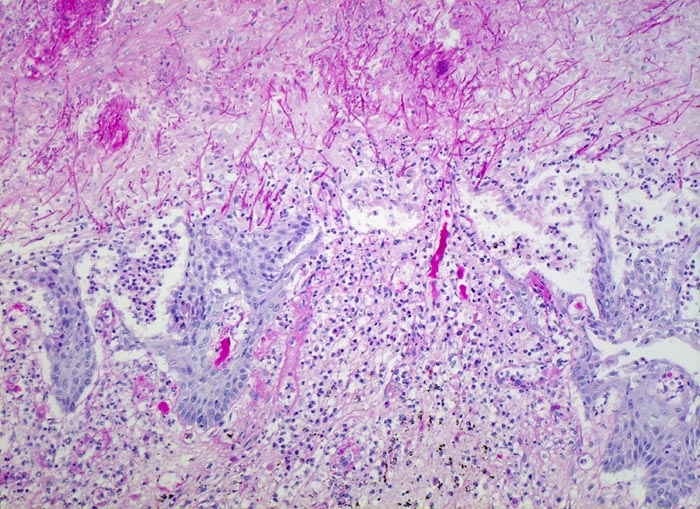

Soorösophagitis

Entzündung infektiös

Oesophagus

Das Plattenepithel ist teils ulzeriert, teils erodiert. Soorpseudohyphen infiltrieren das stehengebliebene Epithel. Dichte Infiltrate von neutrophilen Granulozyten im Epithel.

Mann, 75 Jahre, mit bekanntem multiplen Myelom. Autopisepräparat. Progrediente Dysphagie.

Histologie

100